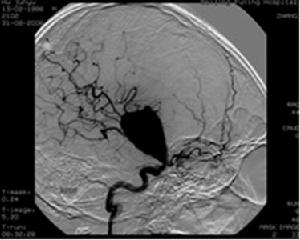

腦血管造影片輕度的動脈狹窄不至於影響其血流量一般認為必須縮窄至原有管腔橫斷面積的80%以上才足以使血流量減少。從腦血管造影片上無法測出其橫斷面積,只能測量其內徑。動脈內徑狹窄超過其原有管徑的50%時,相當於管腔面積縮窄75%即可認為是足以影響血流量的狹窄程度也就是具有外科意義的狹窄。

2.腦血管造影 腦血管造影在腦缺血病的診斷上是不可缺少的重要檢查可以發現血管病變的部位、性質、範圍及程度。應儘量做全腦血管造影,並包括頸部的動脈和鎖骨下動脈必要時還應檢查主動脈弓部如首次造影距手術時間較長術前還需重做造影檢查。腦血管造影具有一定危險性,對有動脈粥樣硬化的患者危險性更大,可引起斑塊脫落造成腦梗死。近年來套用經股動脈插管造影,較直接穿刺頸總動脈造影更安全,且具有高度血管選擇性可選用雙向連續造影包括顱內及顱外循環。

在腦缺血疾病的患者中,有相當一部分是由於顱外血管病變所致動脈硬化引起的狹窄或閉塞具有多發性,可有數條動脈受累,也可表現為同一條動脈上有多處病變。